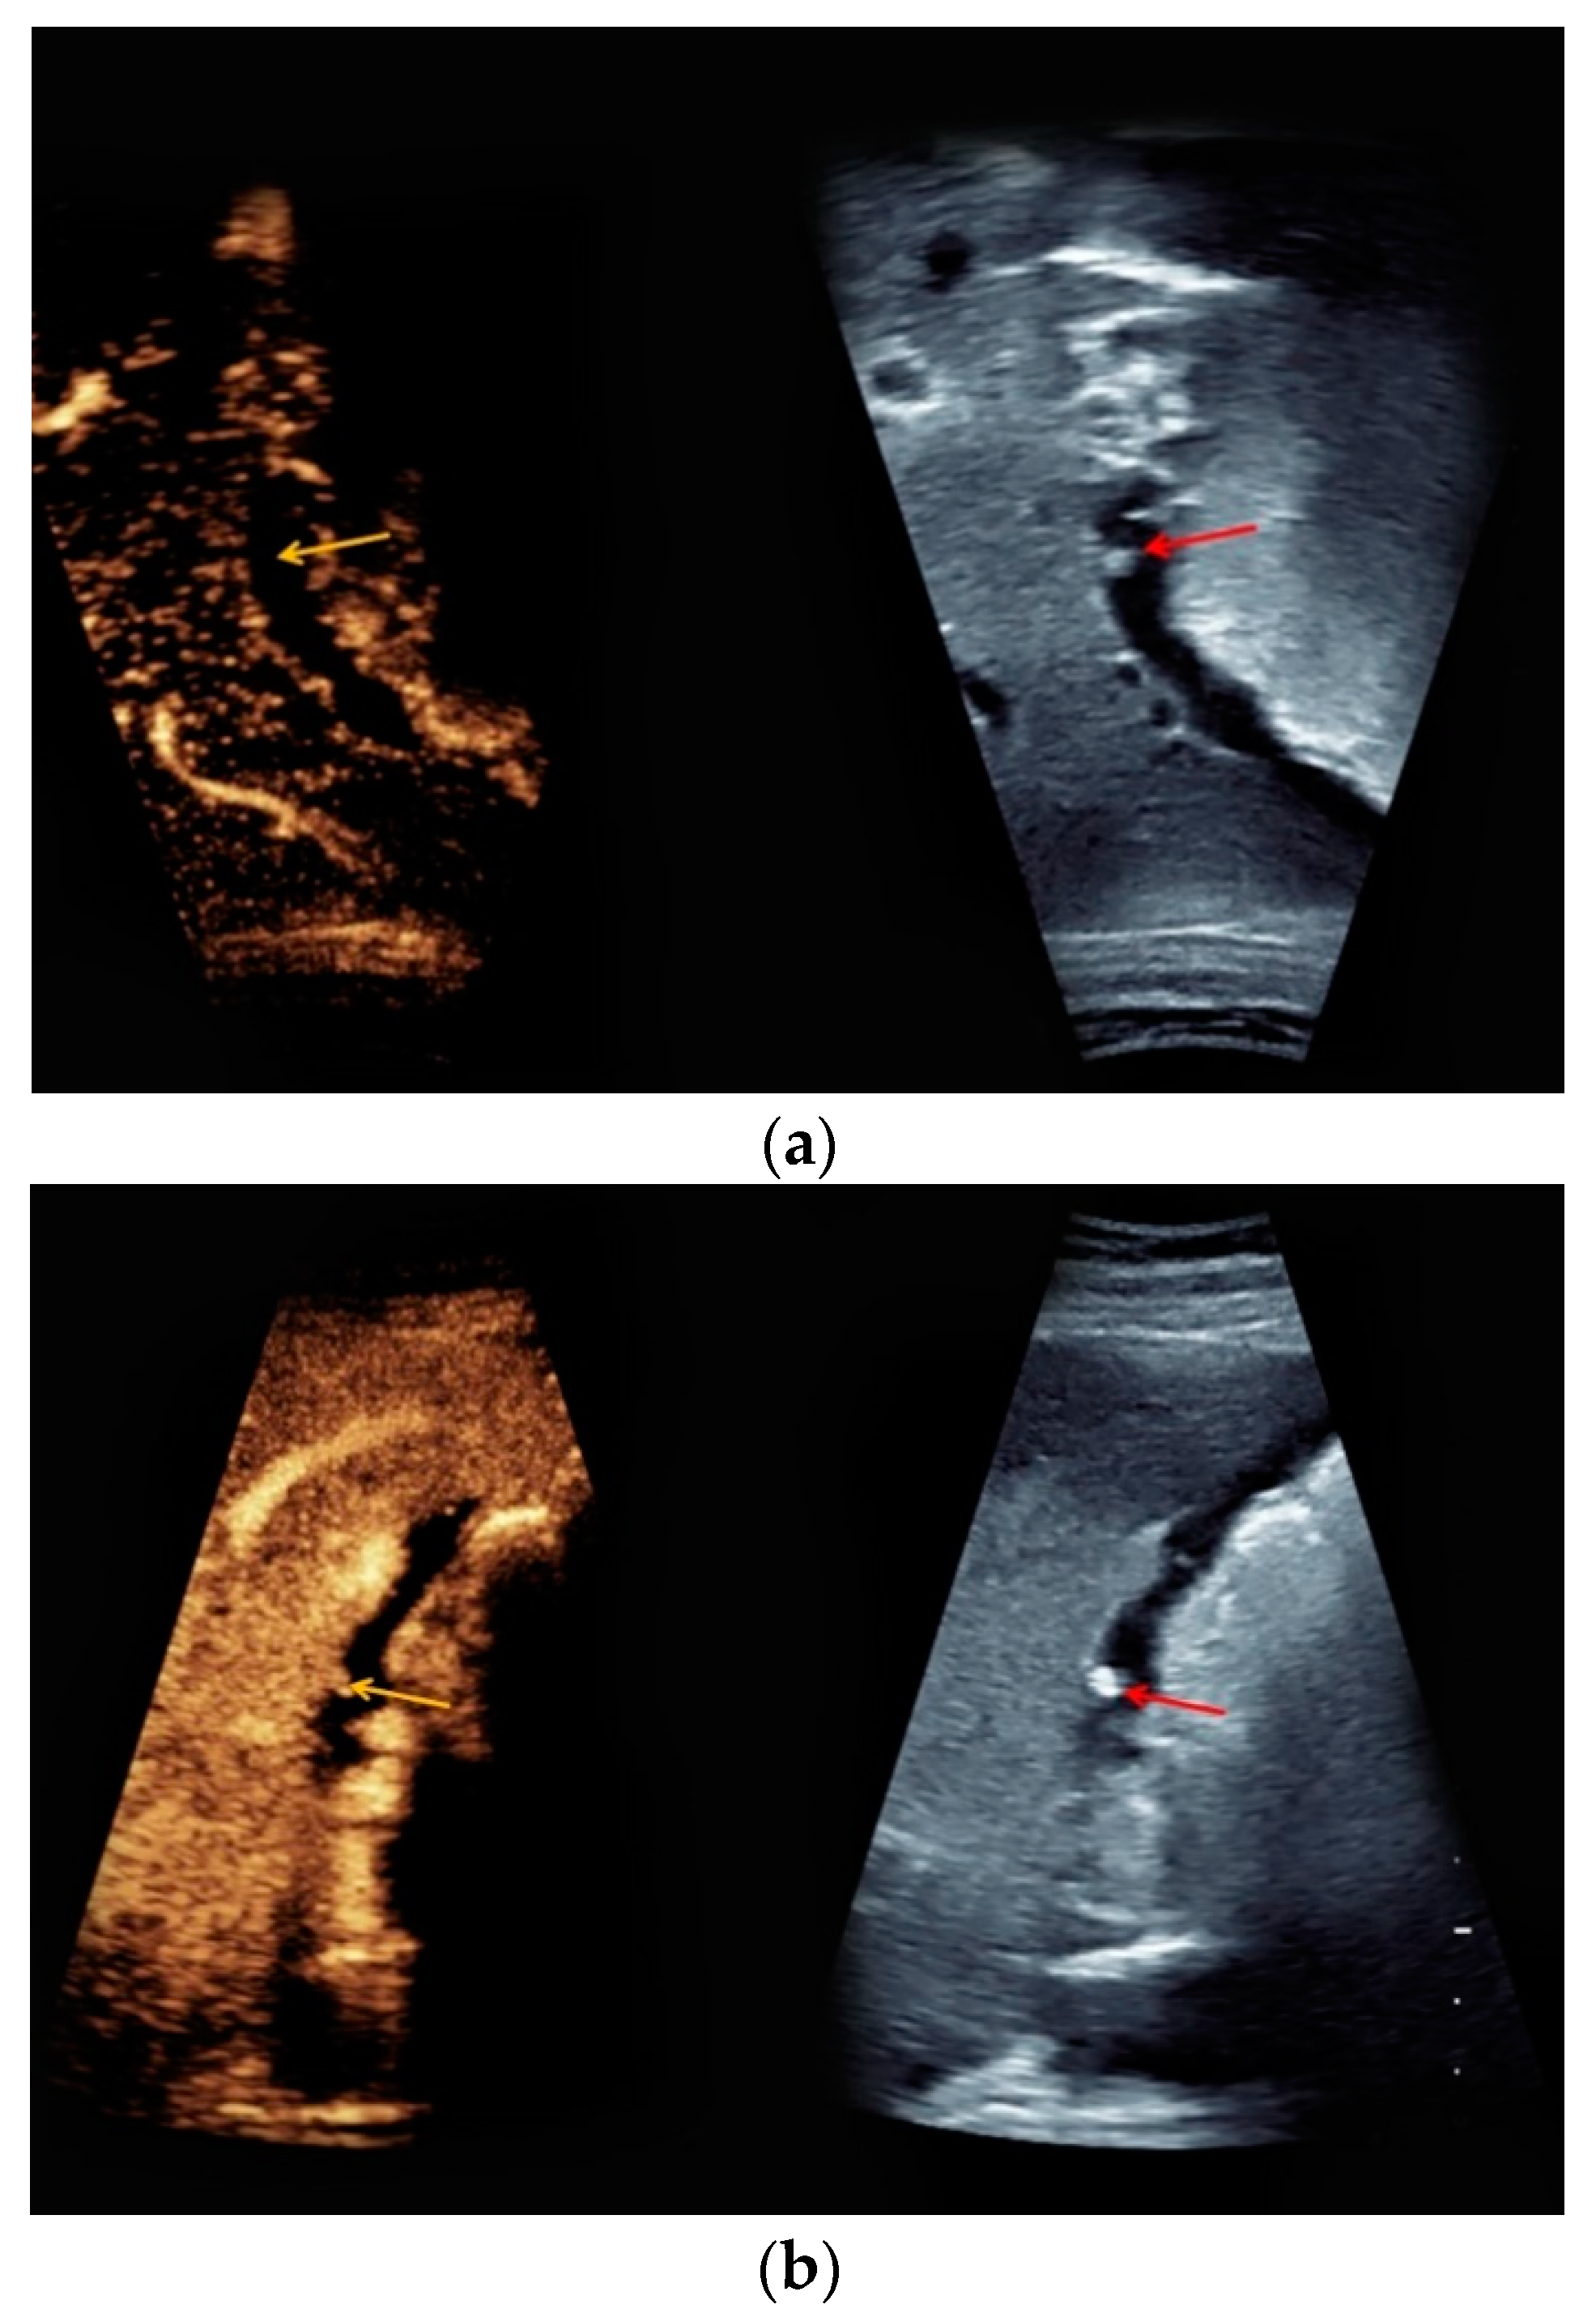

| #5 | 34 | 14 | Superior mesenteric vein thrombosis | B-mode: no abnormalities Doppler: no Doppler signal in the superior mesenteric vein CEUS: only slightly marginal microbubble distribution in the superior mesenteric vein | small superior mesenteric vein thrombosis |